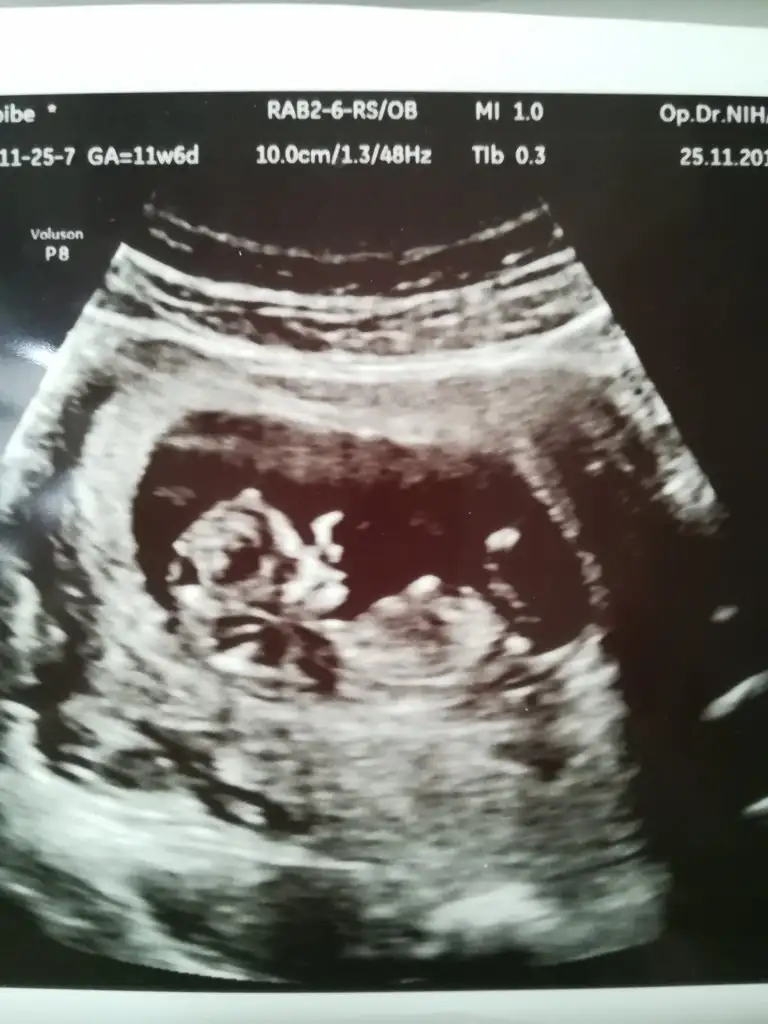

Nub görünmüyor boyutlu olmayan usg paylaşırmısınızMerhaba, bende 11 haftadayim. Tahmin edebilir misiniz?Eki Görüntüle 2558732

KızIkea meyra banada yorum lütfen 11.5 haftalık

11+5 erken daha tabi bizimki usg göre tahminYaaaa :)) şimdi doktordan geldim ama %90 erkek dedi .. hayırlısı neyse o olsun![]()